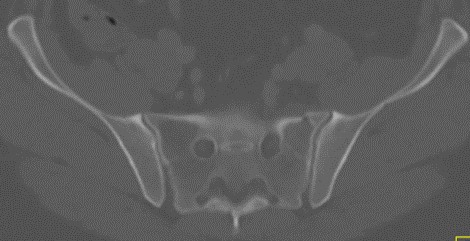

Zone 3 sacral fracture